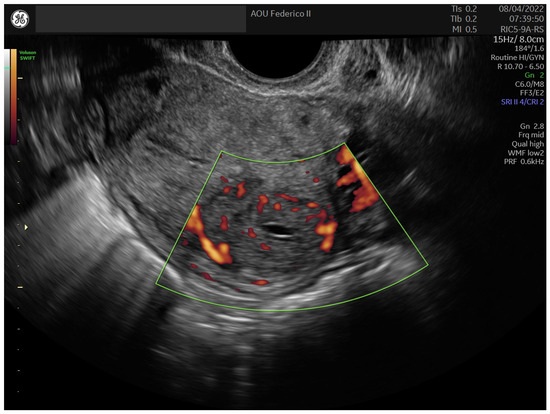

2.2. Case 2